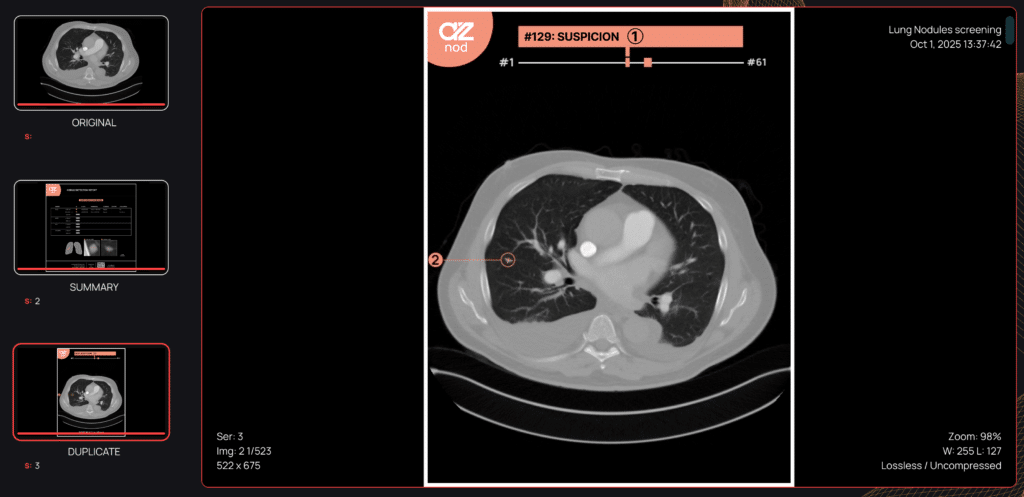

Designed to support lung cancer screening programs, AZnod analyzes the full set of CT scan images to detect pulmonary nodules ranging from 3 to 30 millimeters, regardless of their type (solid, subsolid, or ground-glass). The solution provides standardized characterization, including volumetric measurements, precise diameters, anatomical location, and morphological features, without disrupting existing diagnostic workflows.

Beyond technological performance, the value of AI medical imaging lies in its operational impact. AZnod generates structured radiology reports, prioritizing nodules based on clinical relevance and providing annotated views and anatomical lung maps to facilitate image review.